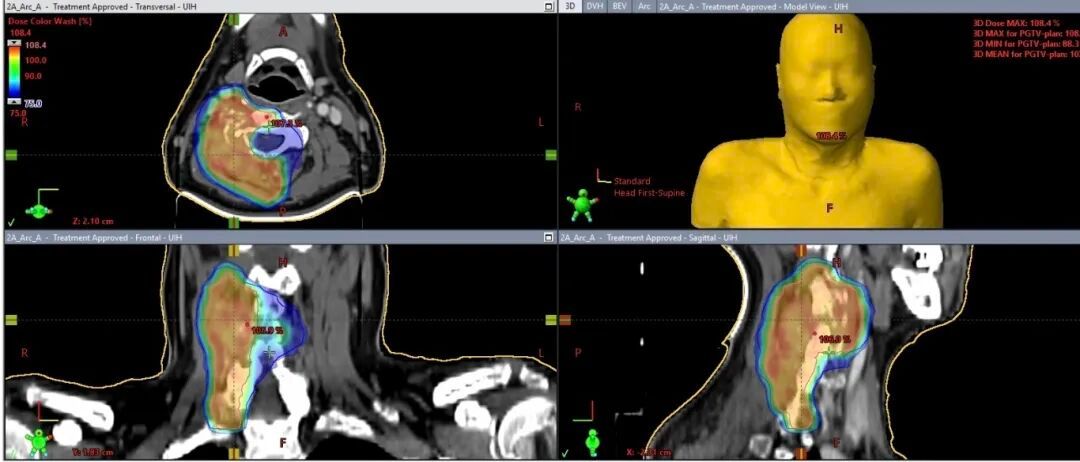

科室团队依托先进的影像引导与靶区勾画系统,实现病灶精准定位,科学规划并严格控制放疗剂量,在有效杀灭肿瘤细胞的同时,最大限度保护病灶周围正常组织,守护患者脆弱的身体机能。团队采用CBCT位置验证技术,将每次治疗的误差精准控制在毫米级,真正实现对肿瘤病灶的“精准打击、最小损伤”,让精准放疗的技术优势转化为守护患者生命的实际力量。